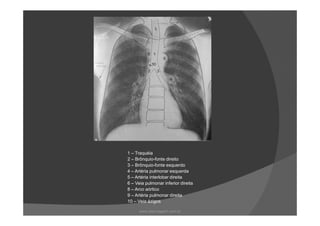

1 – Traquéia

2 – Brônquio-fonte direito

3 – Brônquio-fonte esquerdo

4 – Artéria pulmonar esquerda

5 – Artéria interlobar direita

6 – Veia pulmonar inferior direita

8 – Arco aórtico

9 – Artéria pulmonar direita

10 – Veia ázigos

1 – Traquéia 2– Brônquio-fonte direito 3 – Brônquio-fonte esquerdo 4 – Artéria pulmonar esquerda 5 – Artéria interlobar direita 6 – Veia pulmonar inferior direita 8 – Arco aórtico 9 – Artéria pulmonar direita 10 – Veia ázigos www.playmagem.com.br